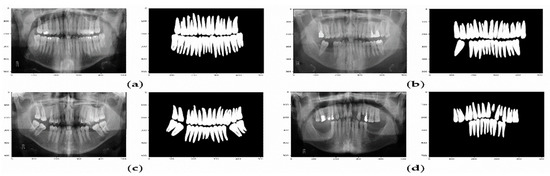

The confusion matrix presented in Table 4 and Figure 8 show that the U-Net model can predict the missing teeth (class 1) perfectly.

Figure 8. Example of predicted masks using U-Net model. (a) The X-ray image and the predicted binary mask for normal teeth. (bd) Various X-ray images and their predicted binary masks for missing teeth.